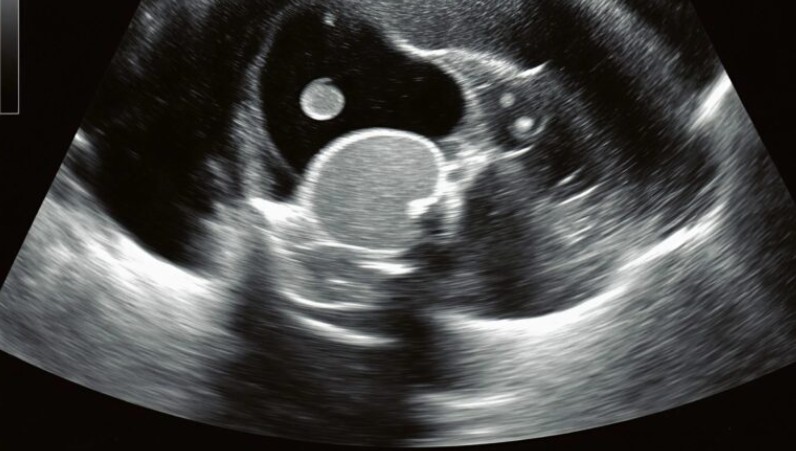

Dans les couloirs de l’urgence, le temps semblait s’être figé. Ma fille se tordait de douleur sur la civière tandis que nous attendions, angoissés, les résultats de l’échographie. Finalement, le médecin est venu vers nous et a prononcé la phrase que nul parent ne veut entendre : « Une opération urgente est nécessaire. » Ce que nous avions pris pour de simples maux de dos était en réalité dû à un calcul rénal silencieux qui s’était progressivement formé. Le calcul s’était déplacé dans le canal, provoquant une douleur intense et un risque vital.